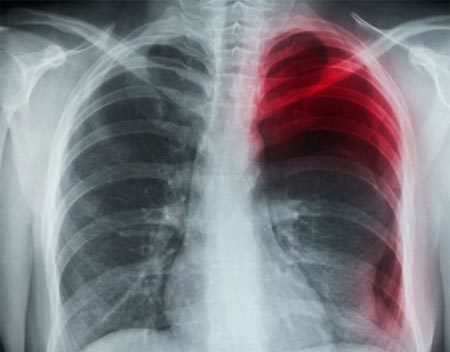

| Ảnh chụp X-quang cho thấy anh Ou bị tràn khí màng phổi tự phát sau khi ngáp. Ảnh: Corbis |

Theo trang ecns.cn, Ou rốt cuộc được đưa vào cấp cứu tại Bệnh viện trung ươngVũ Hán khi cơn đau trở nên mãnh liệt tới mức anh phải chật vật để thở. Các bác sĩ phát hiện, bệnh nhân Ou đã bị tràn khí màng phổi tự phát, hiện tượng xảy ra khi không khí bị mắc kẹt gần một lá phổi.